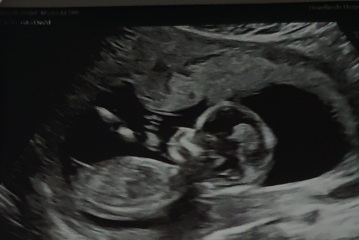

First image at 12 weeks scan for the nub theory

Second image at 20 weeks for possible skull theory

Izzie94x · 15/04/2023 14:02

@BeyondSanity that looks like a girly nub to me!! 💘